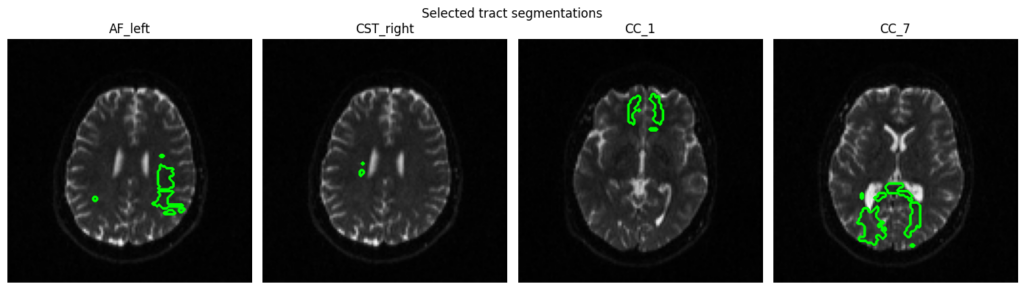

6. Tract Segmentation

Automated white matter tract segmentation via TractSeg using CSD peaks computed with DIPY (rather than MRtrix) to maintain a Python-native implementation.